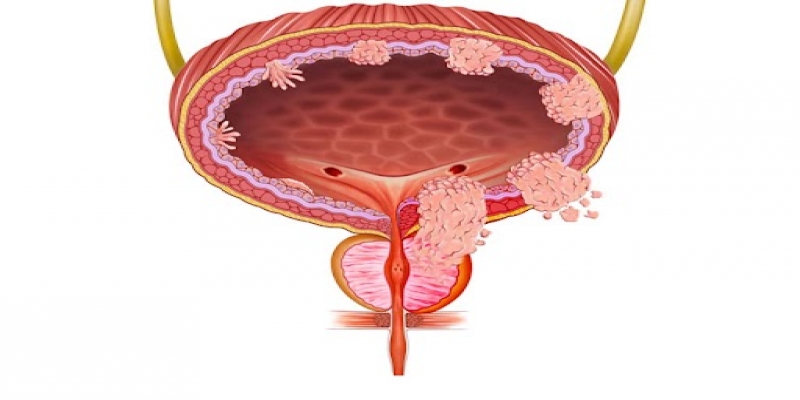

Kasa invaze olmayan mesane kanseri (KİOMK), mesane kas tabakasına ilerlemeyen ancak yüksek tekrarlama riski taşıyan yüzeyel tümörleri içeren bir hastalık grubudur. Mesane kanseri, mesanenin iç yüzeyini döşeyen ürotelyal hücrelerden kaynaklanan malign bir tümördür. Genellikle ağrısız hematüri (idrarda kan) ile belirti verir ve kasa invaze olmayan (yüzeyel) veya kasa invaze olan (derin) olarak sınıflandırılır. Tanı sistoskopi ve biyopsi ile konur, tedavi ise hastalığın evresine ve risk grubuna göre belirlenir.

Kasa invaze olmayan mesane kanseri, mesane iç yüzeyini döşeyen ürotelyal hücrelerden kaynaklanan ve mesane kas tabakasına invazyon göstermeyen yüzeyel tümörlerdir. Mesane kanserlerinin yaklaşık %75’ini oluşturan bu grup, pTa (non-invaziv papillom), pT1 (lamina propriaya invazyon) ve karsinoma in situ (CIS, yüzeyel ancak yüksek malign potansiyelli lezyon) olarak sınıflandırılır. Kasa invaze olmayan mesane kanserleri, yüksek tekrarlama oranına sahip olmakla birlikte, doğru tedavi ve takip stratejileri ile ilerleme riski minimize edilebilir. Tedavi genellikle transüretral rezeksiyon (TUR-M) ve intravezikal kemoterapi veya immünoterapi (BCG) ile desteklenir. Risk grubuna bağlı olarak düzenli sistoskopik takip gerektirir., yüksek tekrarlama oranına sahip olmakla birlikte, doğru tedavi ve takip stratejileri ile ilerleme riski minimize edilebilir. Tedavi genellikle transüretral rezeksiyon (TUR-M) ve intravezikal kemoterapi veya immünoterapi (BCG) ile desteklenir. Risk grubuna bağlı olarak düzenli sistoskopik takip gerektirir.

Mesane kanseri, ürotelyal hücrelerden köken alan ve hem kasa invaze hem de kasa invaze olmayan formlarda seyreden heterojen bir hastalıktır. Kasa invaze olmayan mesane kanseri, tüm mesane kanserlerinin yaklaşık %75’ini oluşturur ve tekrarlama ve ilerleme riski yüksek bir tümör grubunu kapsar. Bu nedenle KİOMK yönetiminde optimal rezeksiyon, doğru risk sınıflaması ve uygun adjuvan tedavi stratejileri büyük önem taşımaktadır.